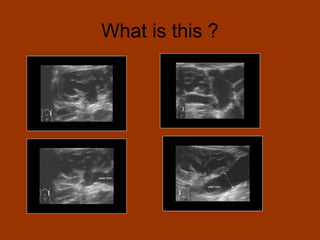

What is this ?

Posterior urethral valve